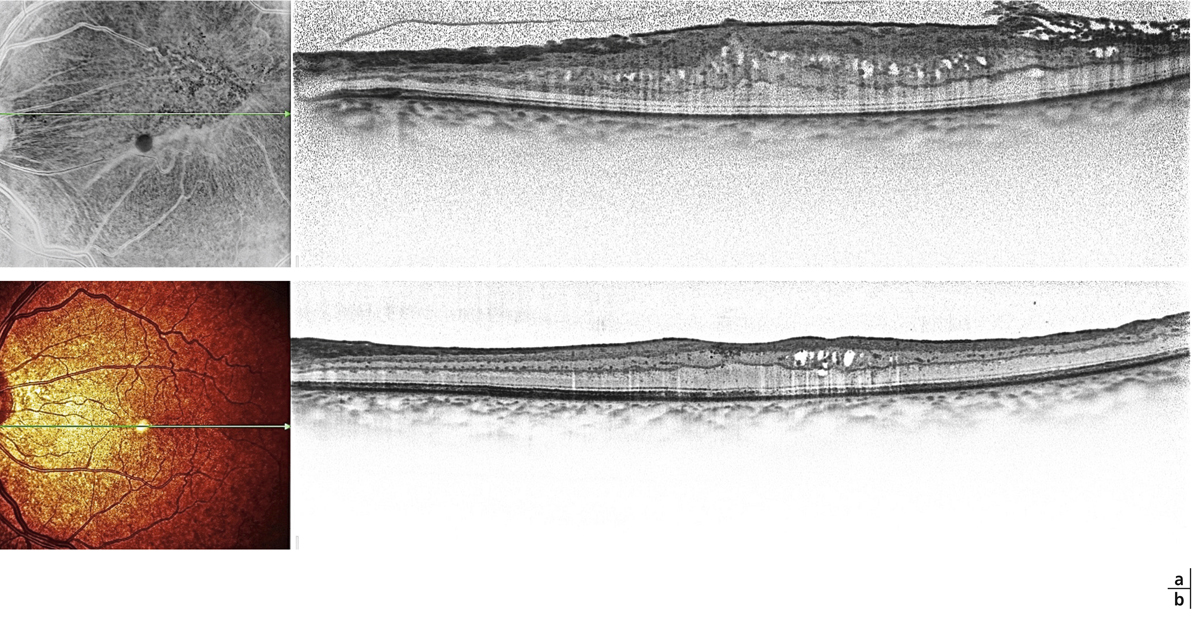

Fig. 13-1 Membrane épimaculaire épaisse avec plis de pleine épaisseur en temporal inférieur.

a. Aspect préopératoire objectivant des cavités pseudo-kystiques dans la couche nucléaire interne. b. Aspect postopératoire montrant un déplissement de la rétine avec disparition des microkystes dans la portion interpapillomaculaire. Les kystes persistent en temporal dans la zone épaissie par la membrane.

Fig. 13-2 Membrane épimaculaire épaisse avec pseudo-trou maculaire.

a. Pli de pleine épaisseur en temporal et cavités kystiques de la couche nucléaire externe en interpapillomaculaire. b. Aspect postopératoire montrant la régression du pseudo-trou maculaire et des kystes de la nucléaire externe.

Fig. 13-3 Membrane avec traction vitréomaculaire.

a. Adhérence vitréomaculaire avec membrane épimaculaire et plissement de la limitante interne. On note de volumineuses cavités kystiques périfovéolaires (œdème cystoïde) associées à un décollement séreux sous-fovéolaire avec interruption de la ligne ellipsoïde. b. Aspect post-vitrectomie–pelage montrant une disparition complète de l’œdème cystoïde et une diminution de l’épaisseur maculaire. La continuité de la ligne ellipsoïde est rétablie.

L’œdème maculaire des membranes peut être initial ou secondaire au pelage. Les membranes les plus actives sont responsables d’un épaississement rétinien visible et mesurable en tomographie à cohérence optique (optical coherence tomography ou OCT) qui peut être assimilé à un œdème intrarétinien diffus lorsqu’il dépasse 300 µ en spectral-domain optical coherence tomography (SD-OCT). La contraction d’une MEM entourant la fovéa modifie ses contours, formant un pseudo-trou éventuellement associé à des cavités kystiques de la nucléaire interne ou externe objectivées en OCT (fig. 13-2). Il est difficile de préciser si l’œdème est la cause de la membrane ou la conséquence de la traction exercée sur la limitante interne [3]. La MEM peut être associée à des hémorragies, ou à des nodules cotonneux témoignant d’une altération du flux axoplasmique dans les fibres optiques. Dans les formes marquées d’œdème, on retrouve sur l’OCT des pseudo-kystes dans la couche nucléaire interne (fig. 13-1) pouvant se propager à la couche nucléaire externe ou s’associer à un décollement séreux rétinien témoignant d’un œdème avancé (fig. 13-3 et 13-4) [4].

On distingue les MEM présentant un œdème initial visible en OCT, sous la forme de kystes des couches internes ou de schisis tractionnel de la nucléaire externe (fig. 13-1 à 13-3), des membranes qui se compliquent d’un œdème post-pelage (fig. 13-4). Compte tenu de la multiplicité des présentations et en l’absence de définition univoque, le tableau de l’œdème maculaire cliniquement significatif représente une forme clinique à rechercher lors de l’évaluation des résultats du pelage. Il s’agit d’une baisse d’acuité visuelle objective ou subjective associée à un épaississement rétinien et à la présence de cavités kystiques visibles en OCT au niveau des couches internes ou externes de la rétine [5].